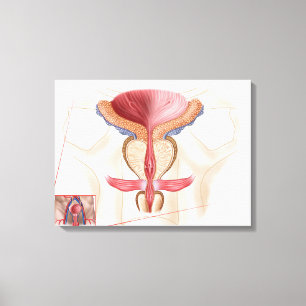

Impressão Em Tela Anatomia Da Terra Prostática

Preço136,00 €